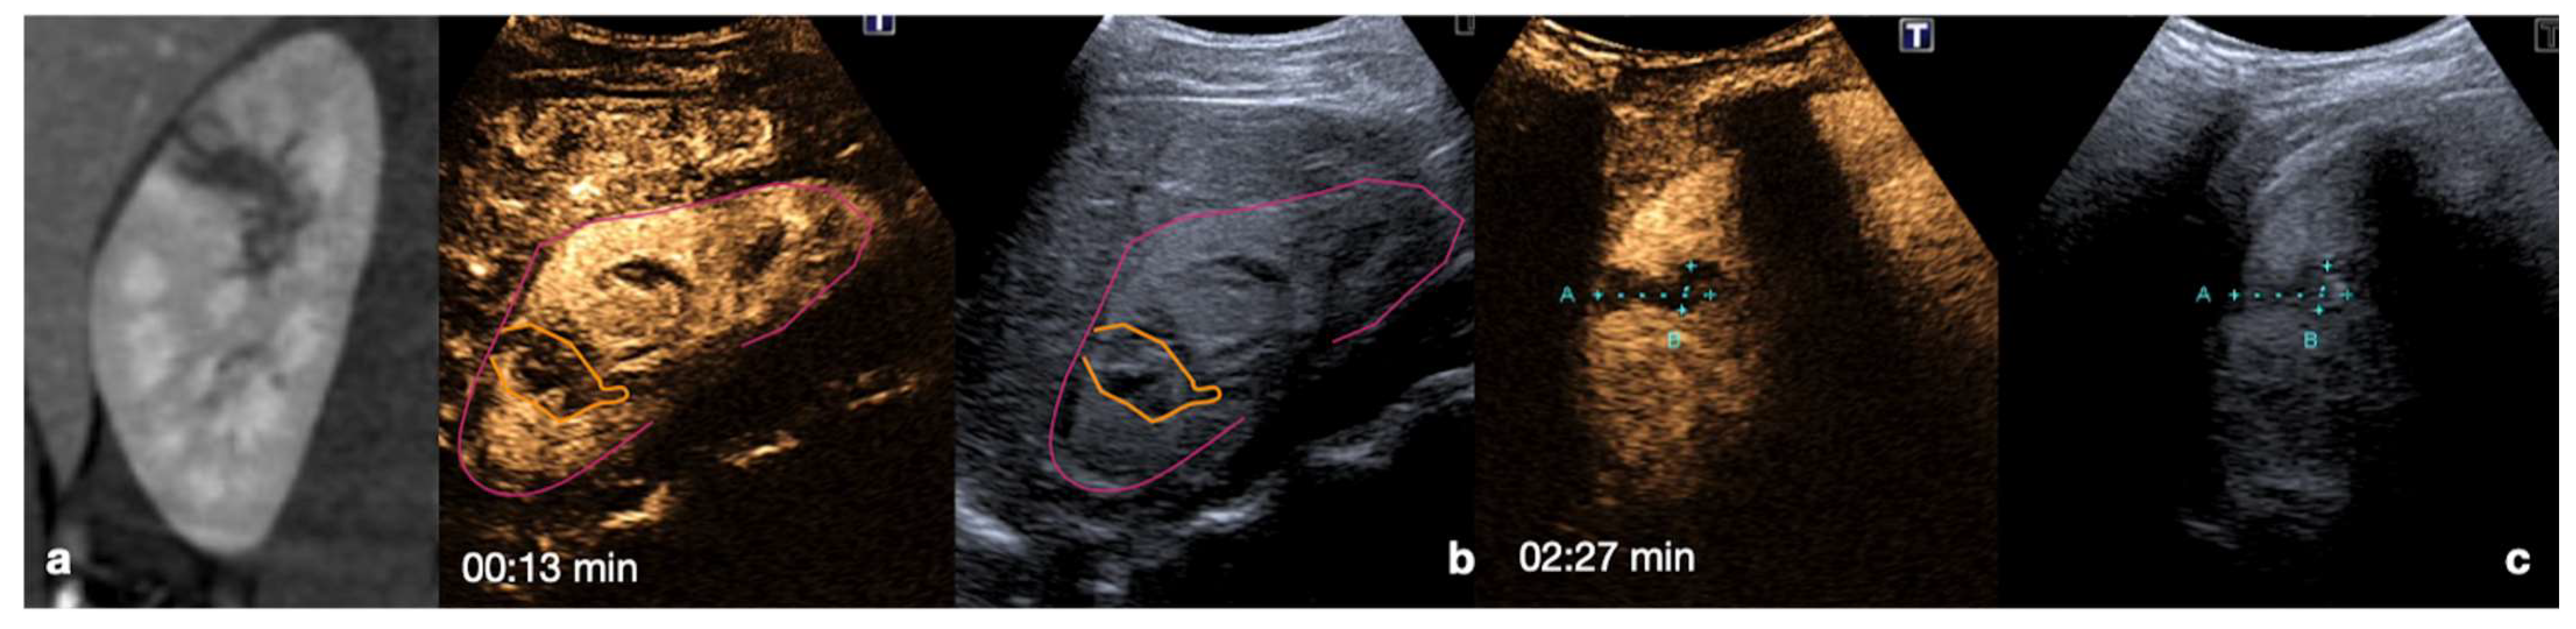

Figure 14.

Admission CT (a,b) and follow-up CEUS (c–o) of a 35−year-old blunt trauma patient with multiple hepatic lacerations. Follow-up CEUS was performed 3 days (c–e), 11 days (f–i), and 20 days (l–o) after the admission CT. Note at CEUS the progressive enhancement of the liver parenchyma in the different phases. The parenchymal lacerations appear as non-enhancing bands (c, orange line), some of them reaching the liver capsule (pink line) (e,i). In the follow-up, it is important to look for possible vascular injuries (absent in this case) in the early arterial phase (f,l). Parenchymal lacerations appear progressively better demarcated, and more hypoechoic. Adopted from ref. [30], 2021, Iacobellis, F.; et al.